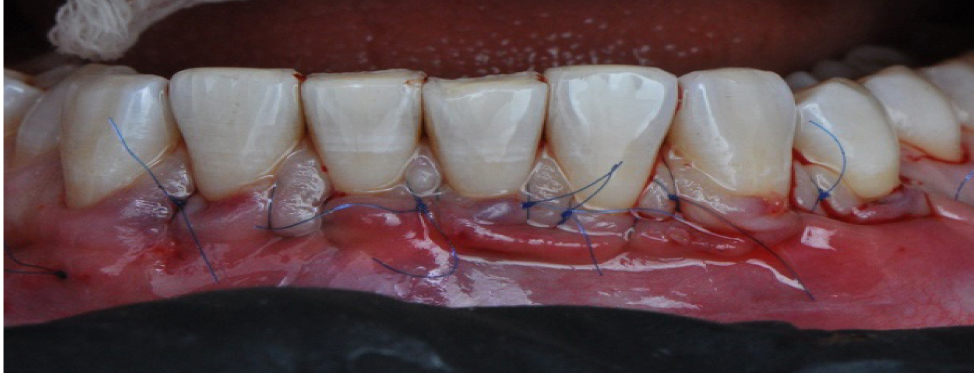

Вначале проводилась антисептическая обработка полости рта 0,05%-м раствором хлоргексидина биглюконата, аппликационная и инфильтрационная анестезии. Затем выполнялись разрезы в области десневой борозды (сулькулярные) через каждую зону рецессии микрохирургическим лезвием с сохранением кончиков десневых сосочков (рис. 2), отслаивание полнослойных лоскутов с помощью микрохирургического распатора. Далее производился забор свободного десневого трансплантата с неба с последующей его внеротовой деэпителизацией и наложением на зону забора параллельных и перекрестных горизонтальных обвивных швов (рис. 3). Позиционирование и фиксация трансплантата в принимающем ложе, ушивание раневой поверхности швами Аллена (рис. 4). Даны рекомендации по послеоперационному ведению: полоскания 0,05%-м раствором хлоргексидина биглюконата 2 раза в день в течение 2 недель, назначены противовоспалительные и обезболивающие лекарственные препараты (НПВС). Повторная явка через день. Швы снимались на 7–10-е сутки. Контрольные осмотры проводились через 3 и 6 месяцев, 1, 2 и 3 года соответственно, оценивалось состояние мягких тканей в области хирургического вмешательства и степень закрытия рецессий десневого края.

Рис. 2. Внутрибороздковые разрезы микрохирургическим лезвием

Рис. 4. Наложение швов Аллена